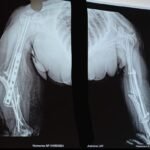

Trauma surgery involves the treatment of fractures and injuries caused by accidents, falls, or high-impact injuries. These injuries may affect bones, joints, and surrounding soft tissues, and often require timely surgical intervention to restore alignment, stability, and function.

Dr Sagar aim for early mobilization after trauma surgery. We also take care of total aseptic precaution with implants.

Complex trauma surgery is required for severe injuries such as multiple fractures, joint injuries, open fractures, or injuries involving previous implants or deformities. These cases need advanced surgical techniques, careful planning, and specialized orthopedic expertise. The aim of trauma and complex trauma surgery is to promote proper healing, restore movement, and help patients return to daily activities safely.